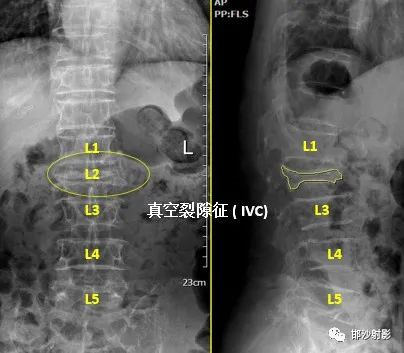

脊柱与骨肿瘤二科病人,女,89岁,腰背疼,翻身时加重,邯郸市曲周县医院X光片显示,腰椎多发压缩性骨折;

我院CT图像:

腰椎多发压缩性骨折,骨质疏松,腰2椎体真空裂隙征;

真空裂隙征(IVC):是椎体缺血坏死的典型表现,前部较后部多见;IVC为渗液时,T1低信号,T2高信号,此征象称为液体征象,高度提示椎体缺血坏死,并可用于鉴别kummell与骨质疏松引起的压缩性骨折,IVC为气体时,MRI均为低信号。